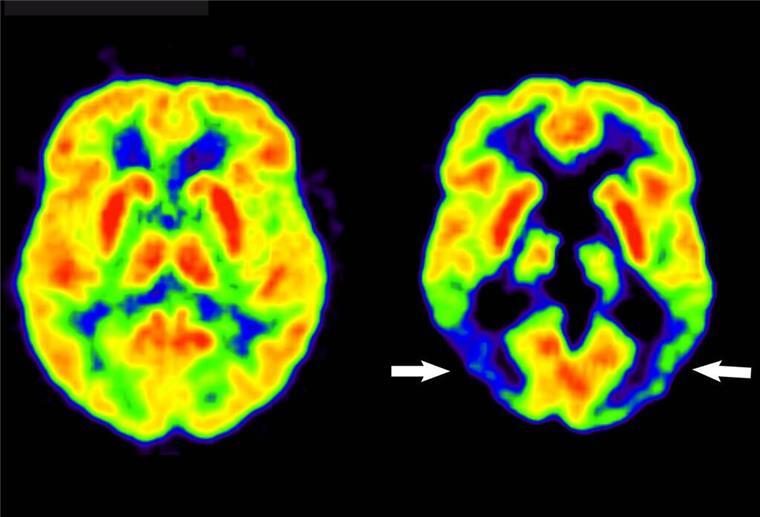

Verschiedene Studien zeigen, dass hoher Alkoholkonsum mit Veränderungen im Gehirn, wie einem Schwund der Gewebemasse, einhergeht. Ein Zusammenhang zwischen schlechterem Abschneiden in Intelligenztests und hohem Alkoholkonsum wurde ebenfalls festgestellt. Es ist jedoch bewiesen, dass hoher Alkoholkonsum auf Dauer das Gehirn schädigen kann, was bei einer MRT-Untersuchung erkennbar ist.

Hoher Alkoholkonsum kann langfristige Schäden im Gehirn verursachen, wie Studien belegen. (Symbolbild)

Foto: Lutz Kracht/MPI